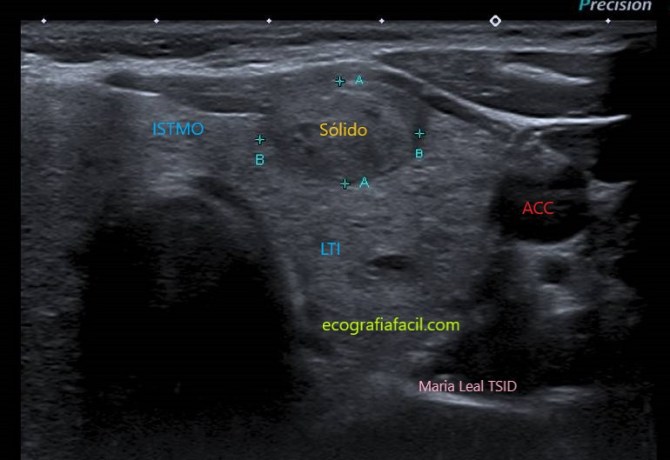

SÓLIDO:

Sólido